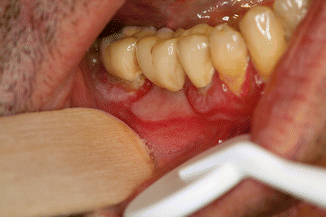

Fig. 35.4

Glazed appearance of the gingiva due to atrophy